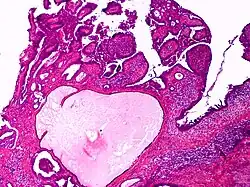

Apocrine gland carcinoma

| Apocrine gland carcinoma, papillary type | |

Apocrine gland carcinoma is a cutaneous condition characterized by skin lesions which form in the axilla or anogenital regions.[1]: 670